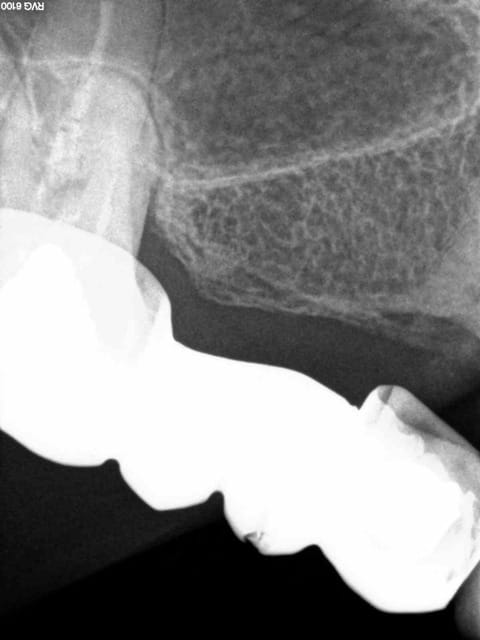

Je ne sais pas sur qui va tomber le déscellement de ce bridge (meme patiente) , mais il (ou elle) va rigoler. -))))